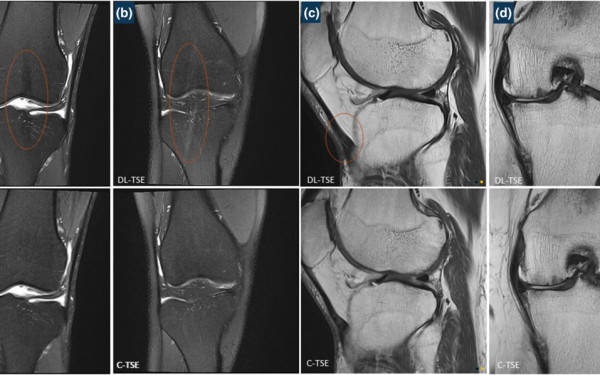

Deep-Learning TSE imaging can provide enhanced knee images

Pacific Radiology doctors and clinical staff recently contributed to a published study on conventional vs deep learning MRI.